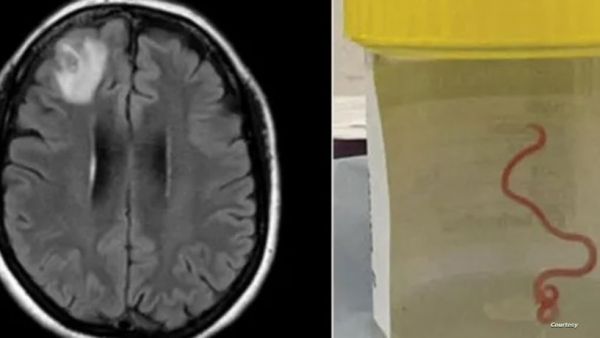

أول حالة في العالم.. أطباء يستخرجون "دودة ثعابين" من دماغ مريضة